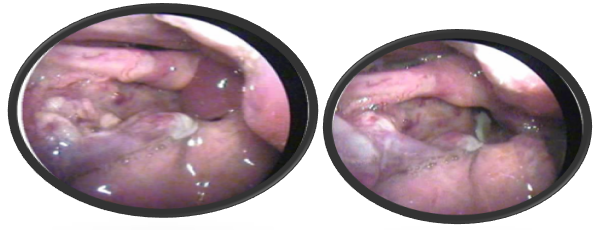

He was admitted in the intensive care unit and monitored for 24hours following which direct laryngoscopy was done under general anesthesia which revealed that the right pharyngo epiglottic fold was transected and supraglottic edema was present. He was conservatively managed with anti inflammatory and anti reflux medications. A video laryngoscopy done six weeks later showed a normal functioning vocal tract.

Figure 5 Video laryngoscopy revealed displacement of bilateral aryepiglottic fold.

Figure 6ballooned up arytenoids and displacement fragment of thyroid cartilage.